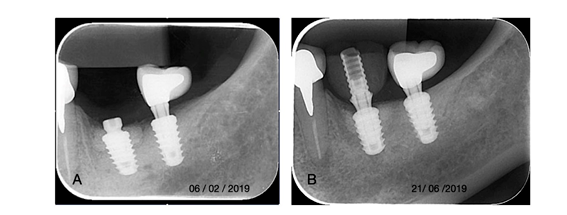

Uma paciente de 54 anos, não fumante, com boas condições de saúde geral, perda de dentes por doença periodontal, e relatando acompanhamento com periodontista privado. Foram realizadas cirurgia mucogengival para aumento de mucosa queratinizada e reabilitação com implantes nas regiões de 36 e 3. Porém, após 2 anos, ela retornou com queixa no implante 36, relato de eventualmente “inchaço”, e no momento com dor e sangramento durante a higiene. No exame clínico foi percebido aumento discreto de volume, secreção, sangramento e profundidade de sondagem aumentada e medindo 10 mm na proximal mesial, 9 mm na proximal distal, 7 mm vestibular, e também 7 mm na lingual. A radiografia periapical, associado aos sintomas e sinais clínicos, indicaram o diagnóstico peri-implantite (Fig. 1a-b). O tratamento proposto foi primeiramente remover a coroa e irrigação local com clorexidina 0,12% e colocar um parafuso cobertura por 4 semanas, com objetivo de fechamento espontâneo da mucosa. Após esse período, foi realizado retalho para exposição do implante, preservando papilas e evitando margem das coroas adjascentes reabilitadas a pouco mais de 2 anos. O debridamento foi realizado com curetas periodontais padrão Gracey Mini-Five 11/12 e 13/14, além de pontas Piezoelétricas para descontaminar e promover sangramento no osso adjacente. Para descontaminação química na superfície do implante, foram utilizados ácido fosfórico 37% por 3min., irrigação com sol. Salina 0,9%, seguido de EDTA 24% (Prefigel) por 2 min., seguido novamente por irrigação sol. salina 0,9% (Fig. 2a-c). Apesar da perda óssea, devido às características morfológicas do defeito, foi realizado procedimento regenerativo para reconstrução do defeito residual. Com a finalidade de manter espaço para regeneração óssea, foi colocado um cicatrizador de 3.5 mm diâmetro x 1.5 mm de altura. A superfície do implante foi umedecida com matriz derivada do esmalte (Endogain). Em seguida, o defeito foi preenchido com osso bovino agregado em colágeno (Extra Graft), e coberto por dupla camada de membrana, sendo a última com endogain aplicado antes da sutura (Fig. 3a-d). O implante permaneceu submerso na mucosa por 5 meses. Após esse período, foi realizado reabertura minimamente invasiva com instalação de coroa provisória feito com pilar temporário (Fig. 4a-b). A coroa temporária permaneceu por mais de 1 ano. Somente após esse período, sem sinais flogísticos e sintomatologia, foi concluída a coroa final. A imagem periapical após 18 meses, e o aspecto clínico com 19 meses, após a reabertura com provisório, demonstram que dentro desse período de proservação o implante se apresenta com saúde e estabilidade tecidual, sugerindo sucesso na proposta terapêutica aplicada (Fig. 5a-b).